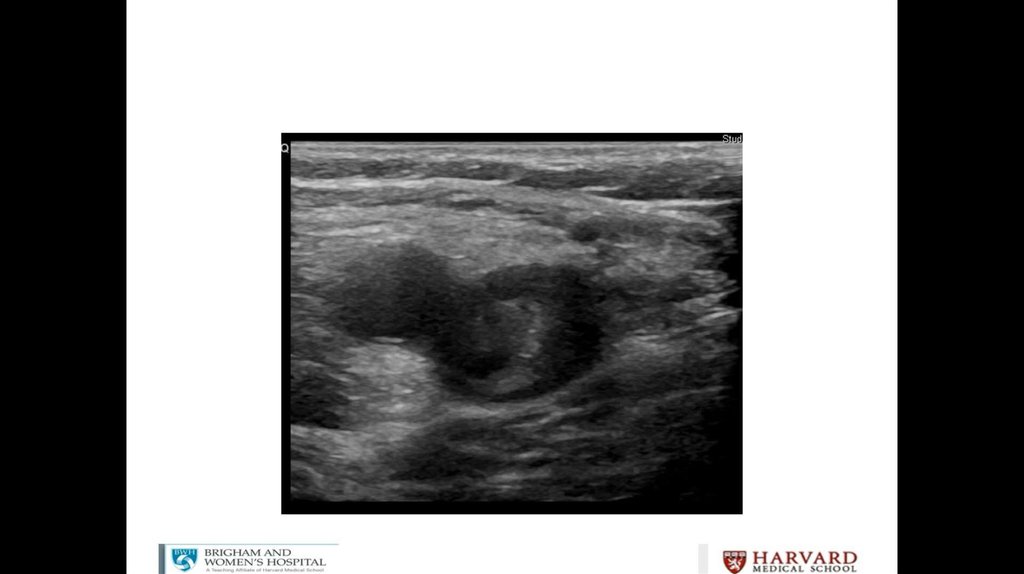

Litrasound in the ICU: What Every Intensivist Should Know